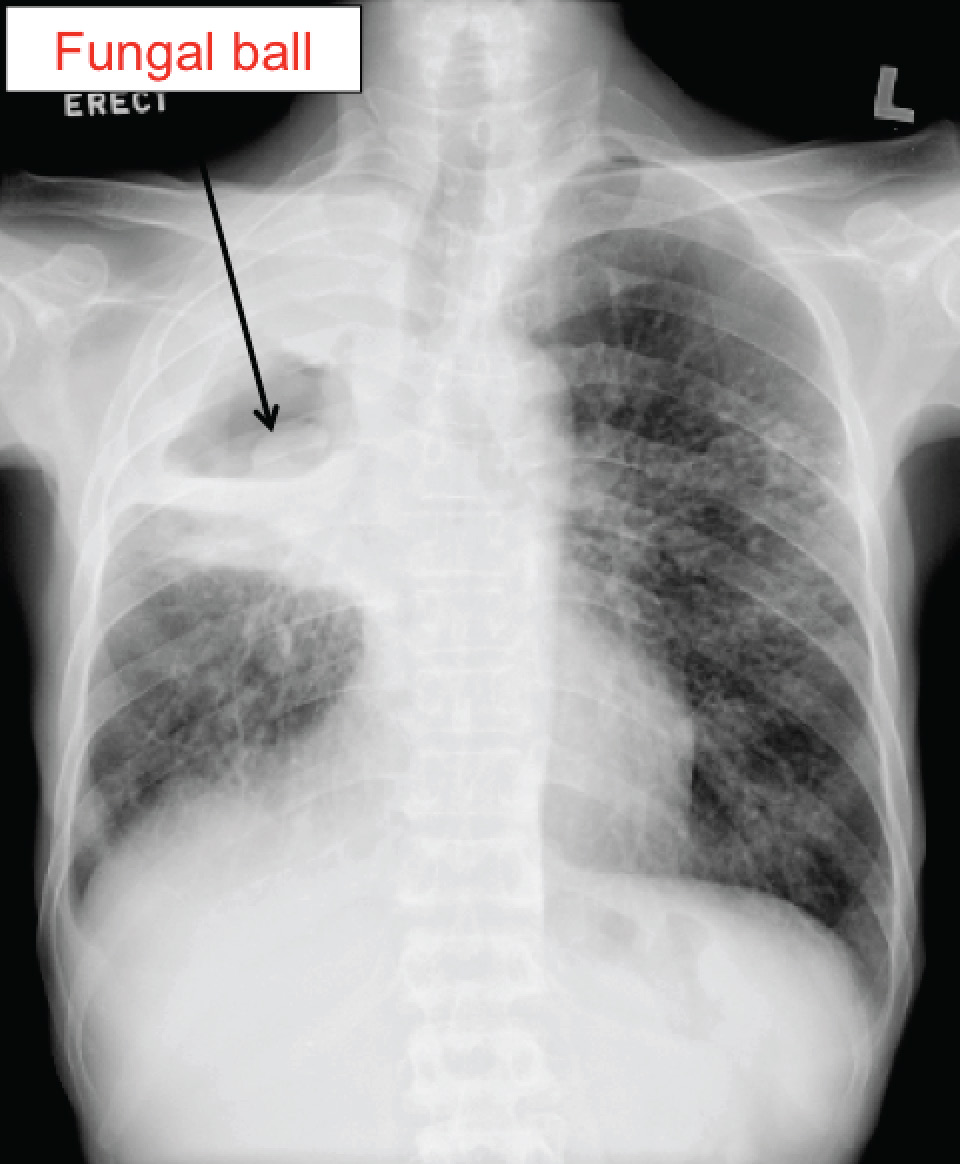

This elderly gentleman had pulmonary tuberculosis 40 years ago. He was also a chronic smoker of 60-odd years, smoking at least 10 cigarettes a day. He presented with paroxysmal coughing for 2 days (more than his usual “smoker’s cough”), accompanied initially by rusty, blood-streaked sputum, but developed frank hemoptysis (coughing out bright red blood) in the two hours prior to his visit to the hospital emergency department. He did not have fever, and his chest X-ray is shown below.

The diagnosis is pulmonary aspergilloma. One can just about imagine a “ball” at the medial aspect of the old TB cavity.